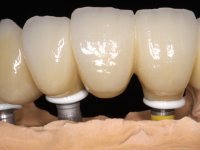

O paciente foi observado conjuntamente e a dúvida que surgiu de imediato foi se seria possível com a regeneração óssea a efectuar poder ser reabilitada naturalmente a zona das papilas interdentárias. Nesse sentido foi feito um enceramento de diagnóstico que contemplaria as duas hipóteses, utilizando ou não a cerâmica gengival. A confecção desse enceramento foi fundamental para expor ao paciente a dificuldade da reabilitação. O wax-up deu origem a um mock-up que foi aprovado pelo paciente e que simultaneamente serviu de guia imagiológica. O caso foi planificado cirurgicamente e realizada uma guia cirúrgica com que foram colocados os implantes. Após 10 semanas foi feita a 1ª impressão para confecção da ponte provisória. Foram criados os primeiros perfis de emergência na gengiva artificial e foi digitalizado o modelo. Por processo de CAD-CAM foi confeccionada uma ponte provisória aparafusada baseada no enceramento de diagnóstico. A ponte trabalhou durante 8 semanas os tecidos moles que foram fielmente copiados numa impressão com técnica de moldeira aberta. Os transferes foram individualizados com resina composta para copiarem fielmente os perfis de emergência criados pela ponte provisória. Confeccionado o modelo de trabalho definitivo, foi realizada uma infra-estrutura em zircónio seguindo a orientação do enceramento de diagnóstico. O assentamento da infra-estrutura foi testado em boca e simultaneamente foi novamente impressionados os tecidos moles com um silicone fluido. Nessa consulta foi feito o levantamento da cor. Os dentes 13 e 23 apresentavam uma saturação anormalmente forte que resolvemos não valorizar, optando por privilegiar a relação com o sector antero-inferior. Foi realizada uma nova gengiva artificial com a impressão que acompanhou a impressão de arrasto com a infra-estrutura. Após a colocação da cerâmica na infra-estrutura foram coladas as meso-estruturas. O trabalho final foi aparafusado lentamente permitindo a adaptação dos tecidos moles.